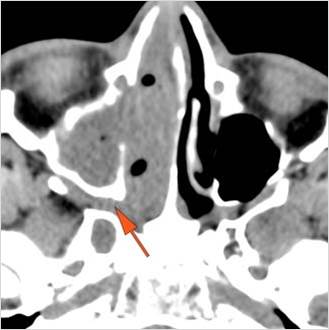

There is infiltration in the posterior nasal cavity or sphenoethmoidal recess that is near to or protruding into the sphenopalatine foramen and pterygopalatine fossa. [Yes/No]

There is evidence of bone erosion along the face of the sphenoid bone or pterygoid base or processes. [Yes/No]